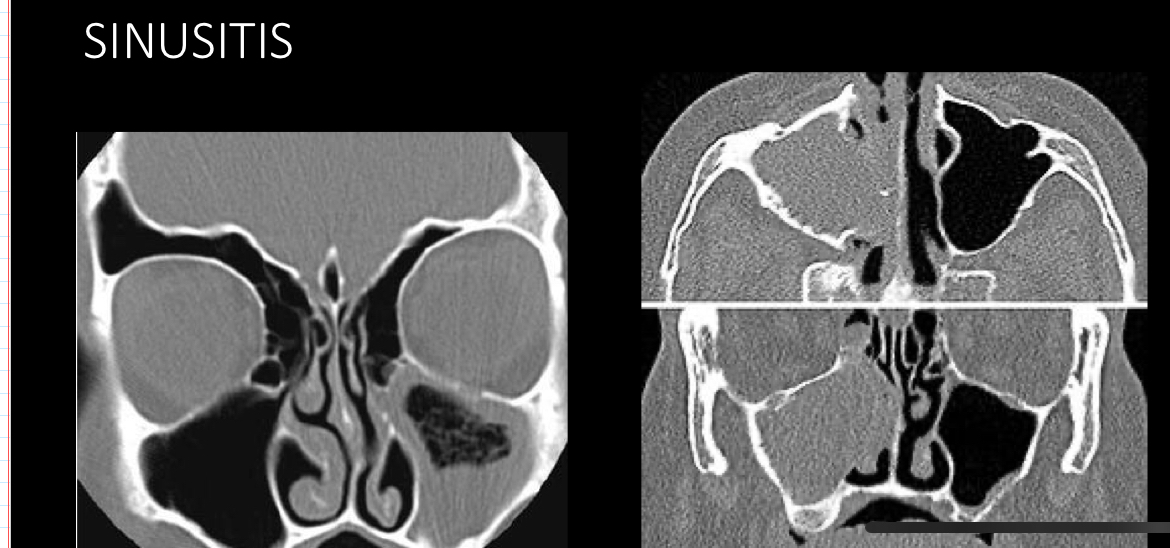

Mejor metodo imagen

A

tc

q se ve en tc

engrosamiento mucosa periferica

Niveles hidroaereos

Permite evaluar oclusion osteomeatal

Desviacion septum

Engrosamiento cornetes:rinitis